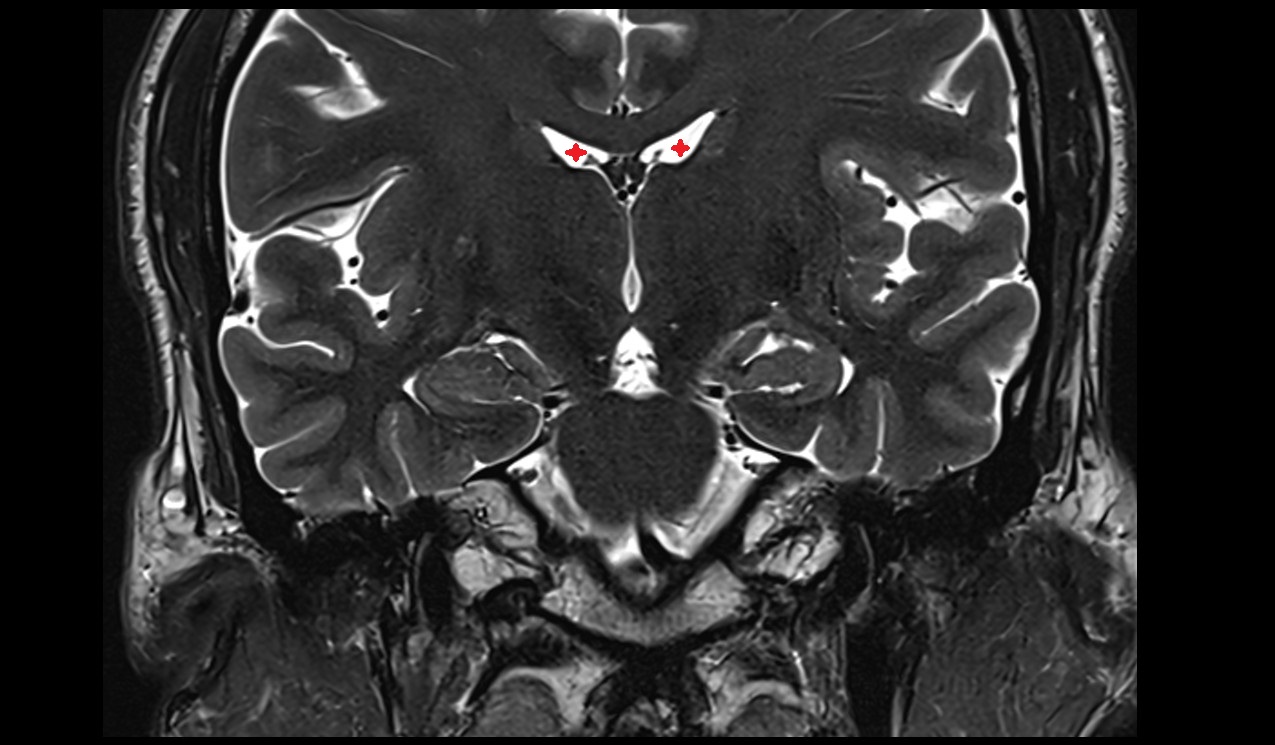

- Frontal horn of lateral ventricle

- Interventricular foramen